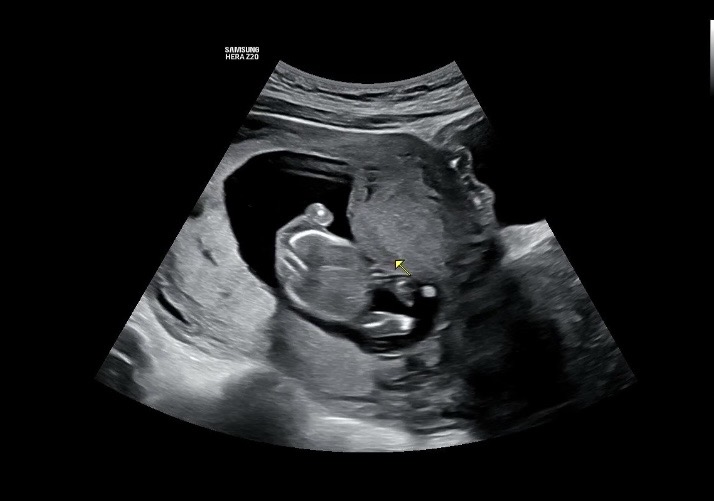

14주3일됬어요. 세컨병원갔더니 뜬금없이 볼록튀어나온게 혹처럼 보이기도 하고 원래 자궁모양인거 같기도 하다고… 괜히 세컨병원가서 걱정만 안고왔네요ㅜㅜ 제가 다니는 병원은 혹에 대한 이야기가 전혀 없었는데…… 사진 어떻게 보이세요??(마우스 가리킨쪽이요)

눌려서 저렇게 보이는걸수도 있구 말씀 없으셨으면 신경 안쓰셔도 될거같아요! 제 초음파도 보시면 아래쪽에 저렇게 혹처럼 크게 튀어나와있어요

초음파볼때 눌려서 저렇게 보이는거 같은데용!! 병원에서 별 말 없으셨다면 괜찮아요 :)